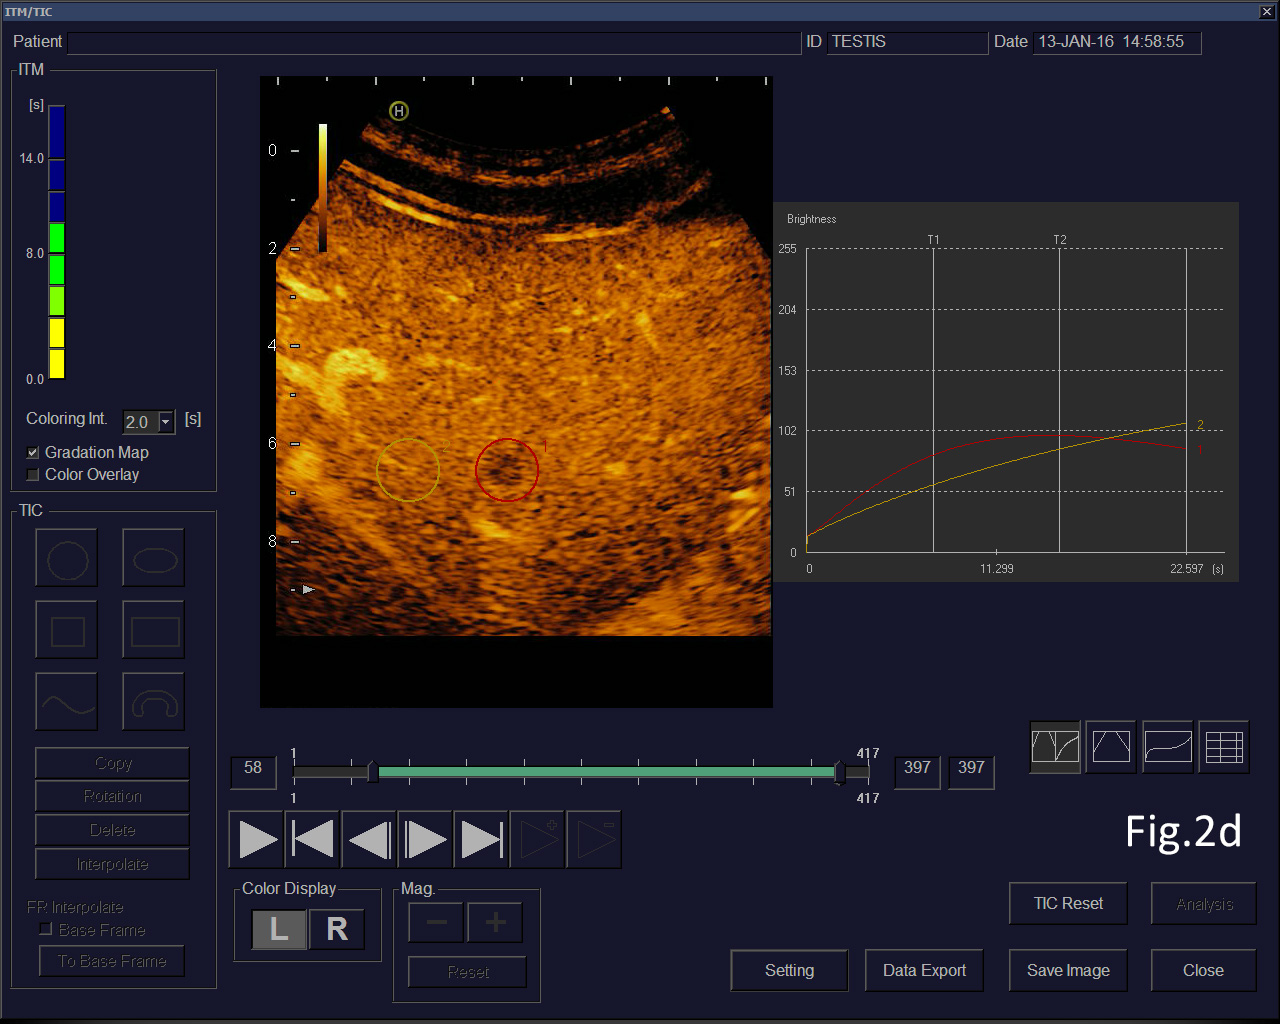

Figure 2: Focal liver lesion using B-mode (a) and contrast enhanced ultrasound (CEUS) in the arterial (b), late phase (c) and CEUS using time intensity curve analysis (TICA) (d). The B-mode ultrasound showed an isoechoic lesion with transducer distal shadowing, somewhat unspectacular. CEUS showed early and slightly hyperenhancing features in the arterial phase and pronounced wash out in the portal venous and late phases indicating metastases and excluding hemangioma [(1)]. The TICA image on the right side of the screen differentiates the initially hyperenhancing lesion (red line) in comparison to the surrounding liver parenchyma (yellow line). In the portal venous phase the red line crosses downward in comparison to the liver parenchyma (yellow line), indicating metastasis [(2-5)].